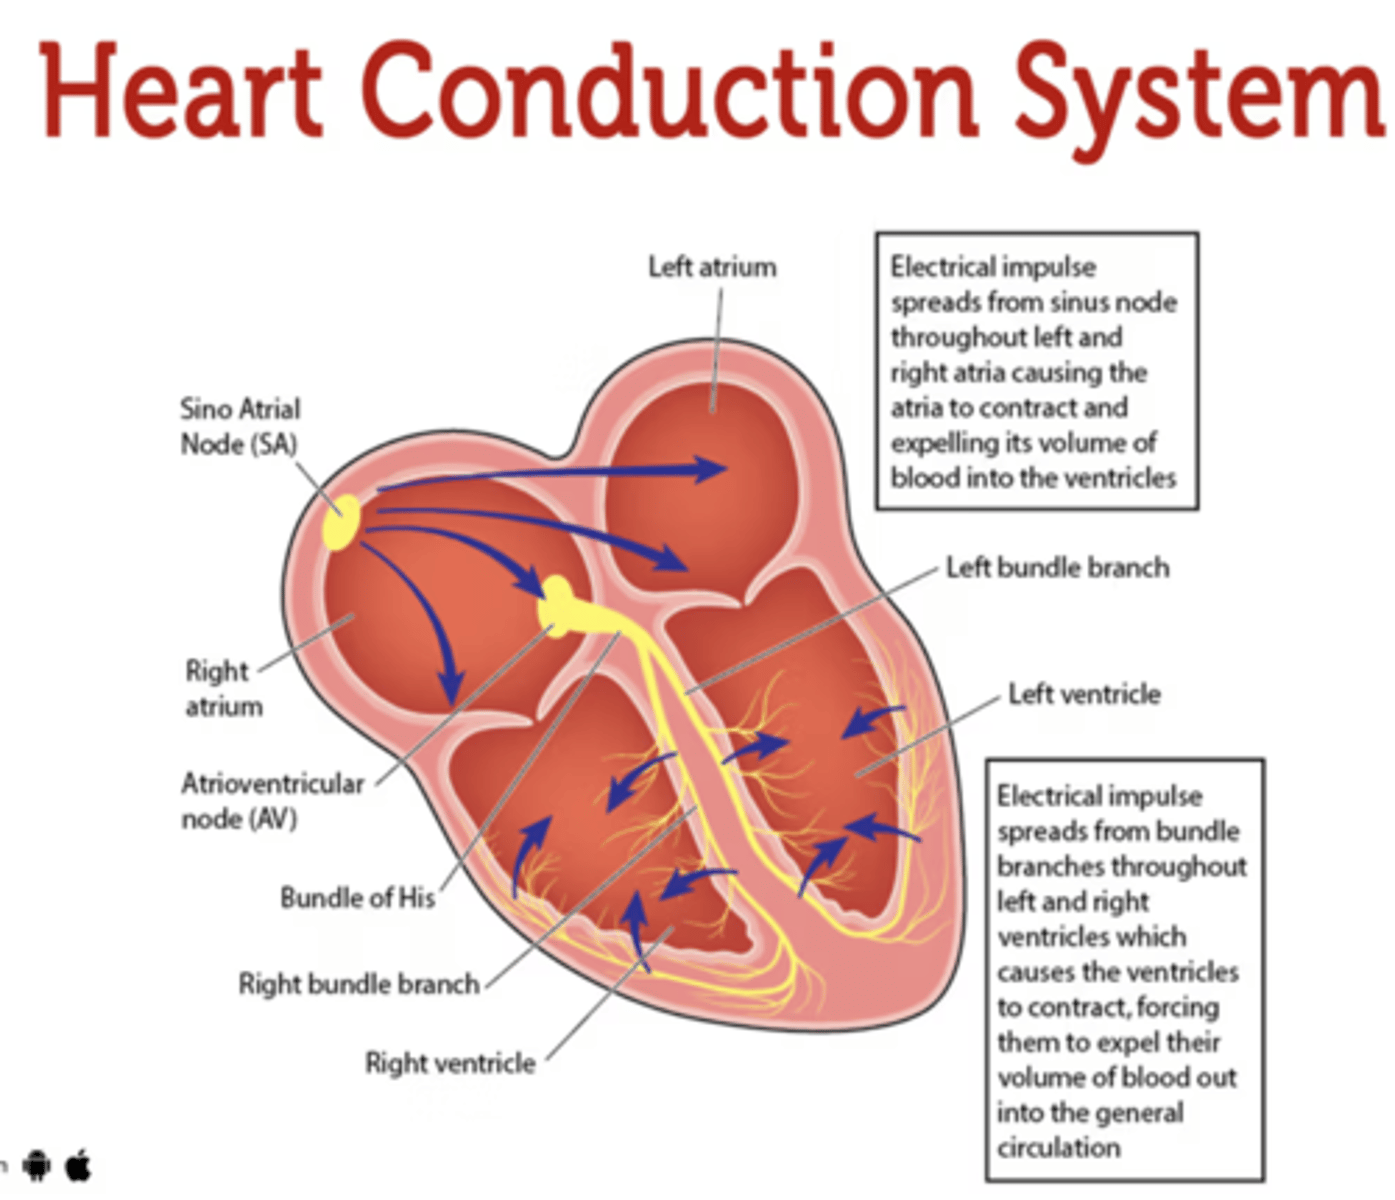

What allows the heart to contract by itself?

The heart possesses a specialized conduction system that gives it the autonomous capacity to contract, allowing it to pump by itself in a correct buffer.

What are the two conduction nodes of the heart conduction system?

. SA node (sinoatrial node)

. AV node (atrioventicular node)

What is the function of the sinoatrial (SA) node?

Pacemaker of the heart

Where is initiated the contraction of the SA node?

SVC (Superior Vena Cava)

passing through the atrium to the AV node

Where is the SA located?

upper wall of the right atrium,

at the junction where the superior vena cava enters

Where is the atrioventricular (AV) node located, and what follows it?

At the level of the atrioventricular septum,

AV node is followed by?

Bundle of Hiss that divides into two branches

Where does Bundle of Hiss ends?

Purkninje fibers

Describe the propagation of waves in the conduction system ?

. SA node sends the initial wave

Passes through the walls of the atria

. Ends at the AV node in the AV septum

. Travels along the Bundle of His

. Reaches Purkinje fibers in the walls of the ventricles

What role does the moderator band play in the conduction system?

Allows the wave to reach the papillary muscles, inducing their contraction simultaneously with that of the ventricles.

REMEMBER: PAPILLARY MUSCLES ACT THROUGH THE CHORDAE TENDINAE TO CONTROL THE TRICUSPID AND MITRAL VALVES.

What is the significance of the Bundle of His in heart conduction?

Branching to the right and left to ensure coordinated contraction of the ventricles.

What are the Purkinje fibers, and what is their function?

specialized conductive fibers in the walls of the ventricles that

facilitate rapid transmission of electrical impulses,

ensuring efficient and synchronized ventricular contraction.

How does the AV node contribute to heart rhythm?

Delays the electrical impulse from the SA node,

ensuring that the atria contract fully to transfer blood to the

ventricles before the ventricles contract.